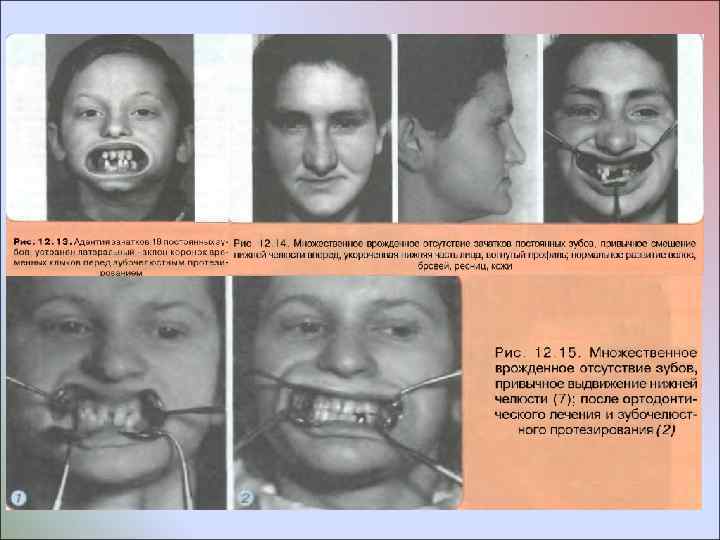

Врожденное отсутствие до 10 постоянных зубов Зубной ряд, в котором отсутствуют отдельные зубы, обычно недоразвит, между зубами имеются тремы, передние зубы противостоящего зубного ряда располагаются тесно, высота нижней части лица уменьшена Адентия зачатков постоянных боковых резцов верхней челюсти. При адентии боковых резцов на верхней челюсти обычно наблюдается диастема, которая подлежит устранению путем мезиального перемещения центральных резцов. В отдельных случаях, чаще при адентии отдельных резцов на нижней челюсти и мезиальном наклоне зачатков клыков, стремятся установить постоянные клыки рядом с центральными резцами, если их бугры имеют округлую форму. По показаниям одновременно с ортодонтическим устранением диастемы перемещают клыки дистально, после чего замещают отсутствующие зубы путем протезирования

Врожденное отсутствие до 10 постоянных зубов Зубной ряд, в котором отсутствуют отдельные зубы, обычно недоразвит, между зубами имеются тремы, передние зубы противостоящего зубного ряда располагаются тесно, высота нижней части лица уменьшена Адентия зачатков постоянных боковых резцов верхней челюсти. При адентии боковых резцов на верхней челюсти обычно наблюдается диастема, которая подлежит устранению путем мезиального перемещения центральных резцов. В отдельных случаях, чаще при адентии отдельных резцов на нижней челюсти и мезиальном наклоне зачатков клыков, стремятся установить постоянные клыки рядом с центральными резцами, если их бугры имеют округлую форму. По показаниям одновременно с ортодонтическим устранением диастемы перемещают клыки дистально, после чего замещают отсутствующие зубы путем протезирования

Если пациент отказывается от ортодонтического устранения зубочелюстной аномалии, то можно изготовить съемный протез, замещающий дефект верхнего зубного ряда и установить нижнюю челюсть без ее привычного смещения вперед, в сторону. Такое лечебное мероприятие способствует нормализации речи, глотания и предотвращает патологические изменения в ВНЧС Врожденное отсутствие отдельных зубов и диастема нередко являются семейной особенностью

Если пациент отказывается от ортодонтического устранения зубочелюстной аномалии, то можно изготовить съемный протез, замещающий дефект верхнего зубного ряда и установить нижнюю челюсть без ее привычного смещения вперед, в сторону. Такое лечебное мероприятие способствует нормализации речи, глотания и предотвращает патологические изменения в ВНЧС Врожденное отсутствие отдельных зубов и диастема нередко являются семейной особенностью